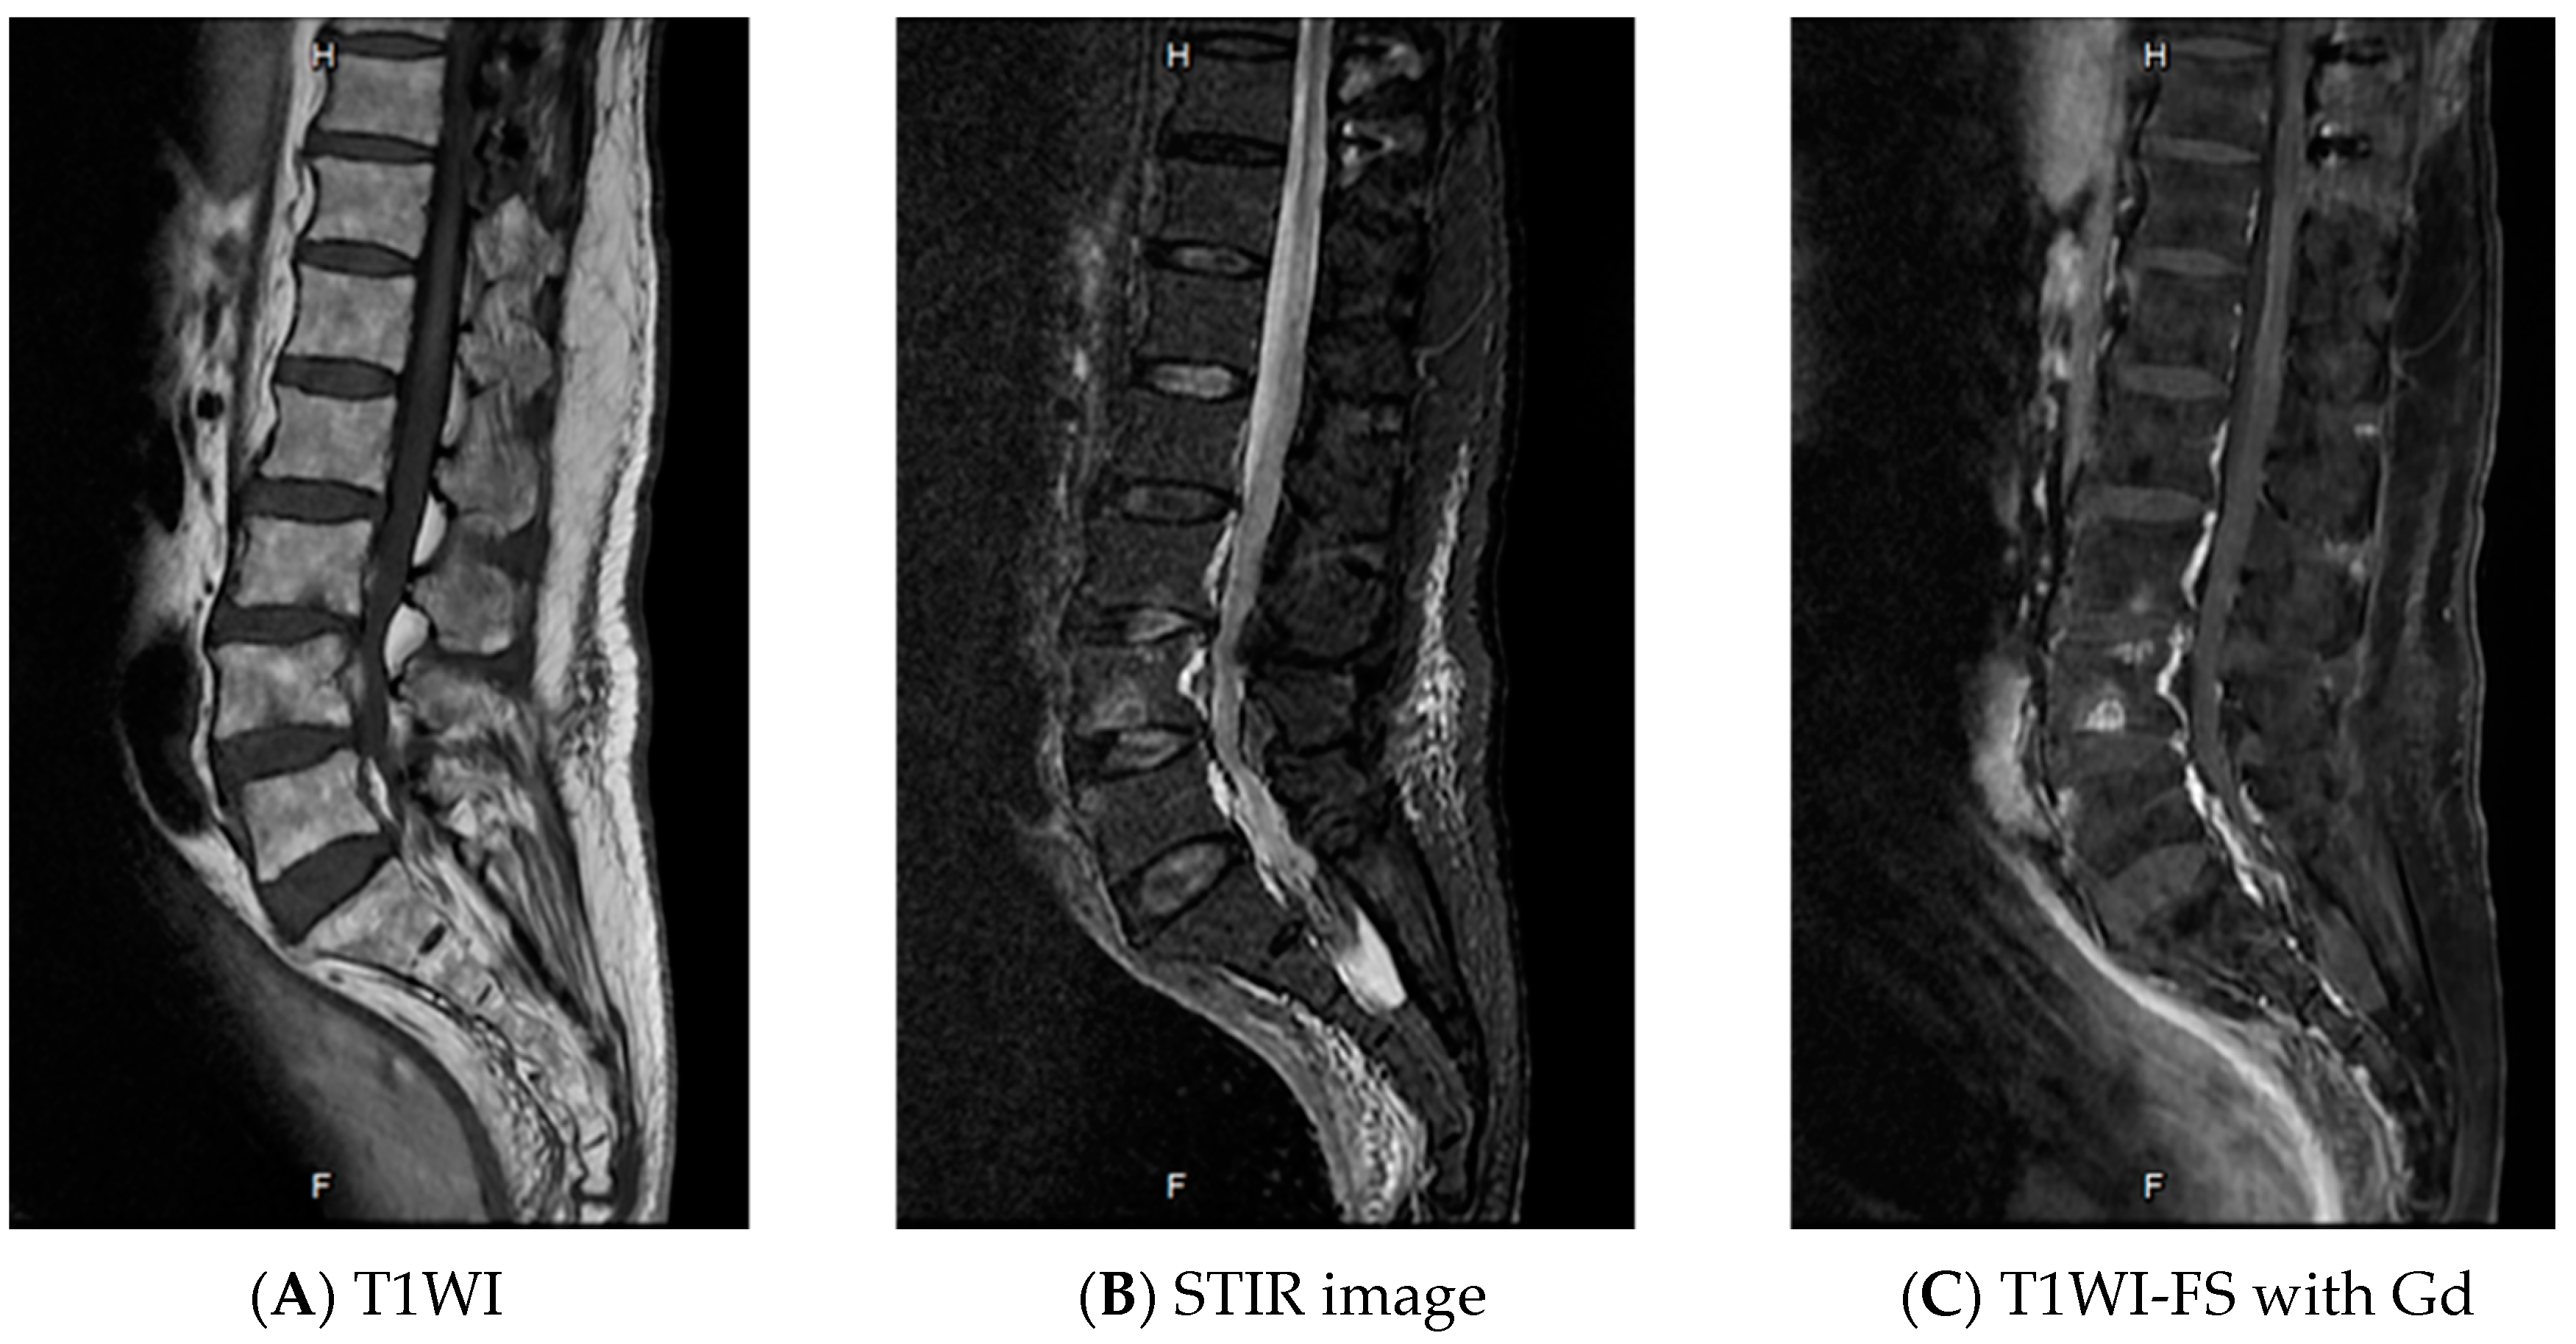

2. Case Report